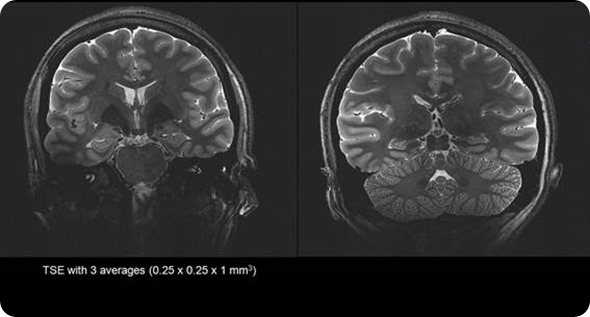

Stronger magnet fields increase the signal-to-noise ratio of the MRI signal. This increase in signal to noise can then be used to increase the spatial or temporal resolution of the image. Simply put, the higher the magnetic field strength, the more detail we can see inside the body.

Most MRI scanners operate between 1.5 Tesla and 3 Tesla. Due to benefits of the increased resolution at higher filed strengths SMT have developed a ground breaking 7 Tesla system, the MAGNETOM Terra. This new system has been designed to meet the demands of both researchers and clinicians.

Due to the extra signal to noise available at 7 Tesla we are able to generate exquisite image quality to show vascularity of the brain without the need for an injection of contrast media often required at lower field strengths.

This allows researchers to identify lesions and bleeds more easily, and the specific areas of the body affected - potentially enabling unprecedented insights into hard-to-diagnose conditions.